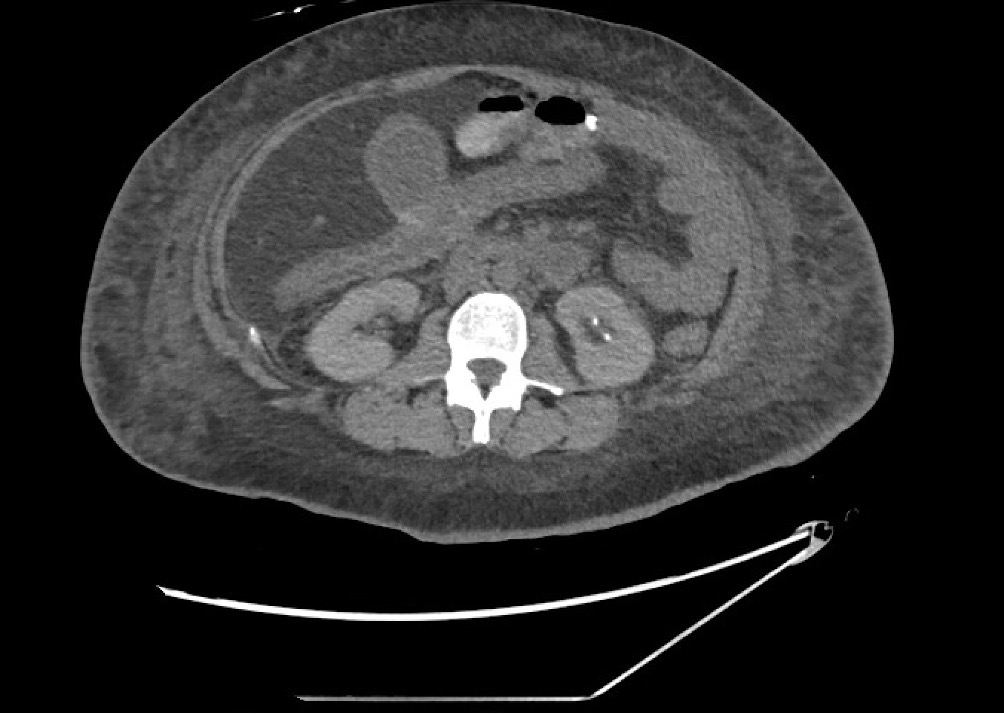

CT scan showing diffuse colitis with no active extravasation